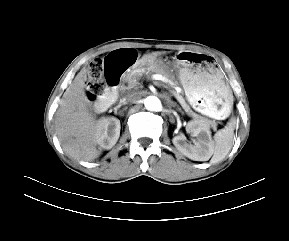

标题: CT19533:病变来源于哪?

患者,男,发现上腹部包块两月余。

病变位于肝胃间隙,实际就是位于小网膜囊(左肝下后间隙),呈轻度不均匀性强化,腹腔内及腹膜后见多发肿大淋巴结。所以我考虑肝胃间隙恶性胃肠间质瘤并淋巴结转移。

病灶强化不显著,灶周及腹膜后见多量淋巴结肿大,考虑淋巴瘤可能,其次考虑间质瘤

病灶与胰腺分界不清,来源于胰腺?

强化后病变与胃壁分界清楚,并且血供不是来源胃壁血管。考虑胰腺颈体癌并腹腔腹膜后淋巴结转移。